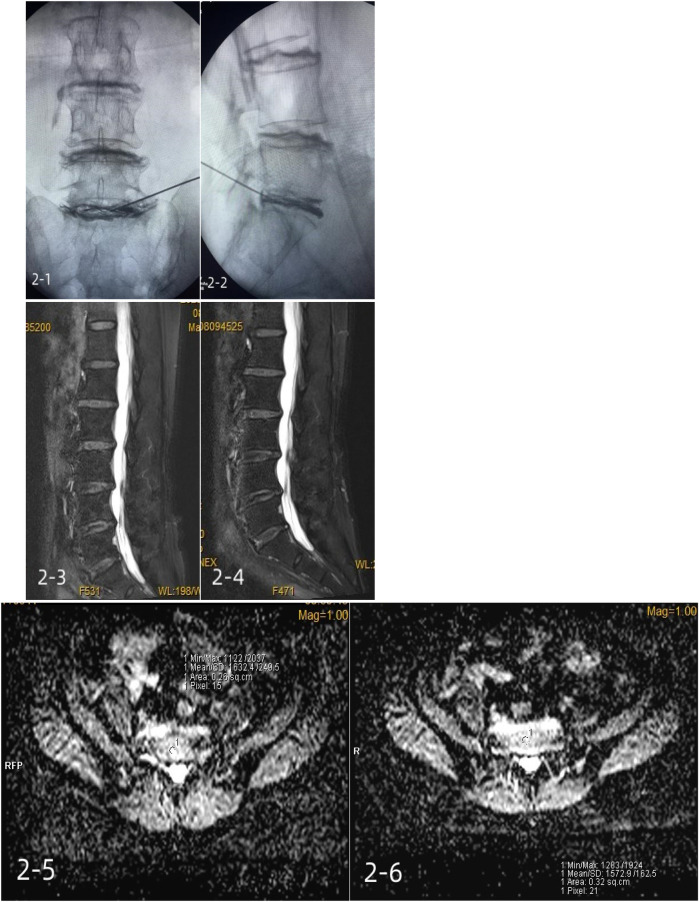

Methods: A total of 40 patients with discogenic low back pain were randomly divided into two groups, with 20 patients in group A receiving platelet-rich plasma injections and 20 patients in group B receiving methylene blue injections. Visual analog scale (VAS) scores, Japanese Orthopaedic Association (JOA) scores, Pfirrmann grades, and MRI apparent diffusion coefficients (ADCs) were recorded in both groups before the injections and 6 months after the injections.

Results: Compared with group B, the postoperative VAS score of group A was significantly decreased, while the JOA score and ADC score were significantly increased (P < 0.05). There was no significant difference in Pfirrmann grade between the two groups after surgery (P > 0.05). In group A, the Pfirrmann grade after surgery was lower than before surgery (P < 0.05), and the ADC score was higher than before surgery (P < 0.05). There was no significant difference in Pfirrmann grade for the patients in group B before and after surgery (P > 0.05), and their ADC score was lower than that before surgery (P < 0.05).